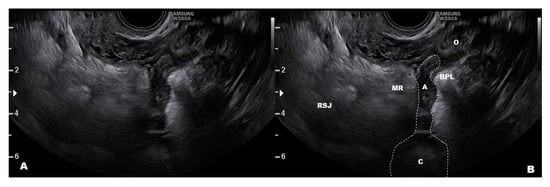

- Leonardi, M.; Martins, W.P.; Espada, M.; Arianayagam, M.; Condous, G. Proposed technique to visualize and classify uterosacral ligament deep endometriosis with and without infiltration into parametrium or torus uterinus. Ultrasound Obstet. Gynecol. 2020, 55, 137–139. [Google Scholar] [CrossRef]